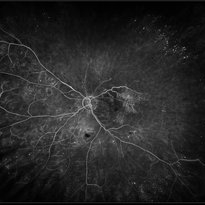

Central Retinal Vein Occlusion with Severe Ischemia

May 22 2016 by Olivia Rainey

Composite fluorescein angiogram of the left eye of a male with a Central Retinal Vein Occlusion with severe ischemia.

Photographer: Olivia Rainey

Imaging device: Heidelberg Spectralis

Condition/keywords: central retinal vein occlusion (CRVO), composite, fluorescein leakage, ischemic CRVO